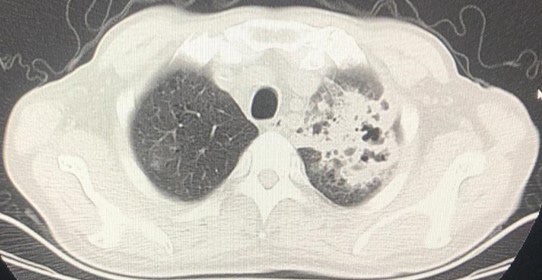

On September 23, he presented to our hospital again with high fever (up to 40°C) and cough. Laboratory tests showed elevated White Cell Count (WBC) of 20.03 X 109 /L neutrophil count of 14.08 X 109 /L and the procalcitonin of 0.86 ng/ml. Haemoglobin was decreased at 77 g/L. Both the fungal G and GM tests were negative. Multiple sputum smear showed a large number of G + cocci, a small amount of G-bacteria. Sputum culture indicated small growth of fungal bacteria. Analysis of blood gas: PH 7.45, PaO2 54.7 mmHg, PaCO2 40 mmHg, Oxygen saturation was 87.8%. Chest CT showed that double lung multiple dense density (Especially the left lung), a bilateral pleural effusion decreased compared with the anterior (Figure 2). Multiple sputum smears found a large number of G + cocci, a small number of Gbacilli, acid resistance stain negative. Pathogenic genetic testing of Bonchoalveolar Lavage Fluid (BALF) suggested that Nocardia cyiacigeorigica,and albicans Saccharomyces, Pneumocystis Jewel (PJ). For special infections in the lungs, we used Meropenem combined with linezolid compound, sulfamethoxazole to fight infection. For the UC, prednisone was continued and thalidomide was added the third IFX infusion was suspended. Then the patient's body temperature was normal, the inflammatory index dropped to normal.

Figure 2: The chest CT scan shows lung multiple dense density (Especially the left lung).

Common opportunistic infections in UC patients include CMV and EB viruses, Streptococcus pneumonia [1], fungus [2]. In this case, this patient quickly developed an opportunistic pulmonary infection after more than 1 month of glucocorticoid treatment and two times of IFX treatment. The results of BALF gene test suggested that the pathogenic bacteria were Nocardia cyiacigeorigica, albicans Saccharomyces, Pneumocystis jewel, which were very rare in UC patients. Nocardia cyiacigeorigica was discovered and redefined in Germany in 2001 by Yassin [3], relatively rare in domestic reports. Laboratory examination and Chest CT lack of specific changes, easy to misdiagnosis and miss diagnosis [4]. Pneumocystis jewel mostly occurs in preterm infants, malnourished infants, and immunosuppressed children and adults [5]. The first-line drug was compound sulfamethoxazole. After the return of BALF results in this patient, we added compound sulfamethoxazole tablets, and the subsequent review of chest CT suggested that the treatment was effective.